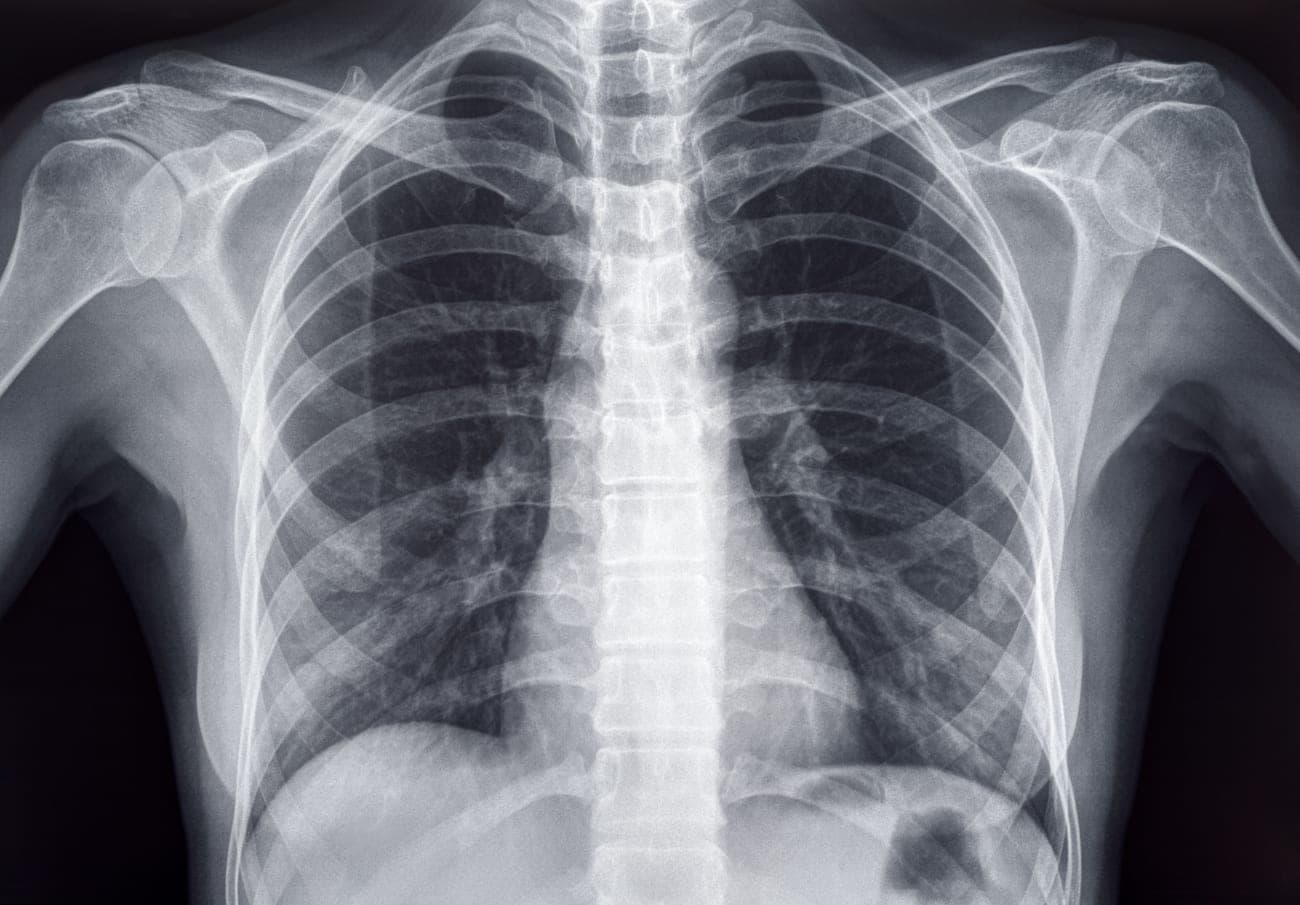

The procedure begins with a thorough preoperative evaluation, including imaging studies such as chest CT scans, pulmonary function tests, and assessments by a multidisciplinary team to determine if the patient is a suitable candidate. Ideal candidates are those who have severe, upper-lobe predominant emphysema and who continue to experience debilitating symptoms despite optimal medical therapy and pulmonary rehabilitation.